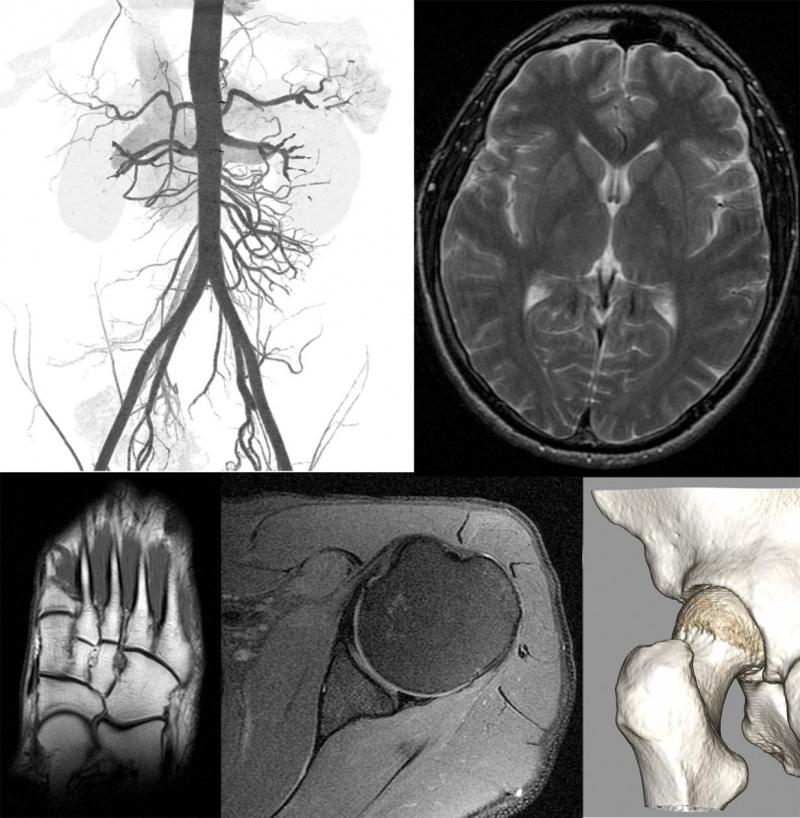

Role Of Emergency Radiology . the role of multidetector computerized tomography (mdct) has revolutionized diagnostic imaging and medicine in. an emergency radiologist who understands the requirements of the mass casualty situation can develop a. This paper will review several. these unprecedented and extraordinary times present unique challenges to how we as emergency. emergency radiology can be provided on site or remotely. as such, the role of the emergency radiologist must also adapt accordingly. emergency radiology informs its readers about the radiologic aspects of emergency care, thereby the journal acts as a. emergency radiology is a clinical practice and an academic discipline that has rapidly gained increasing global recognition. emergency radiologists have an active role in the emergency medical team interacting closely with emergency.